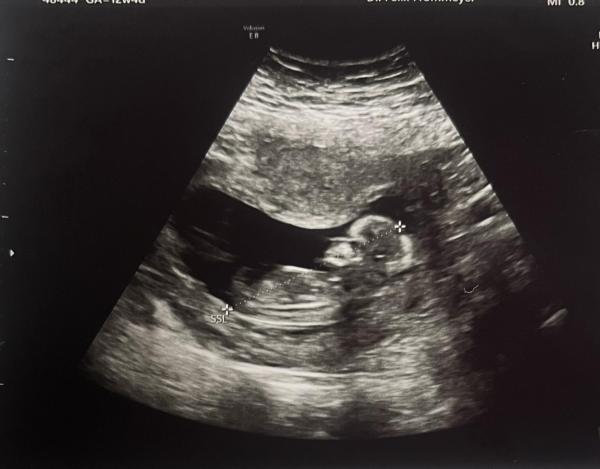

Liebe Kiki,  bei deinem Bild aus der 11ten Woche konnte ich so üüüberhaupt nichts erkennen. Hätte bei dem Bild sogar eher gedacht, dass es eher Arme und Hände sind. Aber erkennen kann man auf dem Bild von deinem letzten Beitrag nichts. Also ich zumindest. Zumal in der 11 Woche die Geschlechter wirklich noch sehr identisch aussehen.  Leider sind auch die Bilder üüüberhaupt nicht Nub Theorie mäßig brauchbar, das Bein ist sehr weit davor.  Beim zweiten mit extrem heran Zoomen und Augen zusammenkneifen..  kööönnnteee man evtl. eine kleine Gabelung erkennen, die eher bei einem Mädchen sind. Aber das ist jetzt wirklich bei den Bildern wie ne Münze werfen 😂😅 Aber ist doch schön, wenn du im neuen Jahr den nächsten Termin hast wird man vll. das Geschlecht erkennen können und ihr startet ins Jahr mit einer Offenbarung 😁

Nein, leider sind seine Bilder so garnicht vorteilhaft 😔 Und ich verstehe vollkommen, dass verschiedene Nubs von den Leuten gesehen werden.  Bei dem ersten hätte ich gedacht: oh. Kööönnnte ein Junge sein. Beim zweiten dachte ich es auch erst und dachte dann: es könnte aber auch zum Bein gehören und hab dann diese gaaanz leicht angedeutete Gabelung gesehen. Aber wie schon gesagt: bei deinen Bildern ist es echt wie ne Münze zu werfen.  Aber Nub Theorie ist halt eben auch nur eine Theorie 🙆‍♀️. Damals sagte sie bei der Feindiagnostik, dass so ein Parallel verlaufender und nach unten zeigender Nub eher für ein Mädchen sprechen würde.    Wir bekommen aber ganz klar einen kleinen Jungen 😂

Ich war einfach mal so frei in deinen Bildern ein zu zeichnen, warum du unterschiedliche Nubs von den Leuten gesagt bekommst.  Dieses erste Bild sieht halt doch schon sehr nach Jungen aus. Über dem vermeindlichen Nub noch dieser kleine Strich und es steht recht hoch und nicht so sehr parallel zur Wirbelsäule    Das zweite Bild, da habe ich dir die suuuper leicht angedeutete Gabelung gezeigt, die ich meine.  Gucke mir jetzt deine Bilder auch nicht weiter an 😂😂😂. Bin echt richtig hin und her gerissen